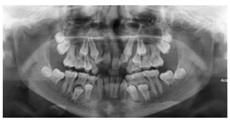

根尖片示:11自根中向远中弯曲约35°,属Ⅱ类弯曲牙,牙根发育至Nolla9期,21牙根发育至Nolla9期,腭侧见两颗正置锥形多生牙;12、22牙根发育至Nolla9期。

CBCT示:上颌恒牙胚萌出间隙不足,根据Moyers混合牙列分析法,牙弓现有长度为177.4 mm,牙弓应用长度为181.6 mm,拥挤度为4.2 mm。42缺失;11、21、22发育至Nolla9期;55、16、65、46冠部低密度影及牙本质中层,根管内未见高密度充填影,根尖周未见明显异常。53、63牙根吸收不足1/3,13、23发育至Nolla8期。

头颅侧位片示:下颌相对颅底位置靠前,趋向Ⅲ类错

,上下切牙舌腭向倾斜,骨龄CS1起始期。